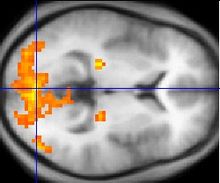

The exact cause is unknown. Although research suggests the likelihood of a genetic basis, there is no known genetic etiology and brain imaging techniques have not identified a clear common pathology. There is no single treatment, and the effectiveness of particular interventions is supported by only limited data. Intervention is aimed at improving symptoms and function. The mainstay of management is behavioural therapy, focusing on specific deficits to address poor communication skills, obsessive or repetitive routines, and physical clumsiness. Most children improve as they mature to adulthood, but social and communication difficulties may persist. Some researchers and people with Asperger's have advocated a shift in attitudes toward the view that it is a difference, rather than a disability that must be treated or cured.

Asperger syndrome appears to result from developmental factors that affect many or all functional brain systems, as opposed to localized effects. Although the specific underpinnings of AS or factors that distinguish it from other ASDs are unknown, and no clear pathology common to individuals with AS has emerged, it is still possible that AS's mechanism is separate from other ASDs. Neuroanatomical studies and the associations with teratogens strongly suggest that the mechanism includes alteration of brain development soon after conception. Abnormal migration of embryonic cells during fetal development may affect the final structure and connectivity of the brain, resulting in alterations in the neural circuits that control thought and behaviour. Several theories of mechanism are available; none are likely to provide a complete explanation.